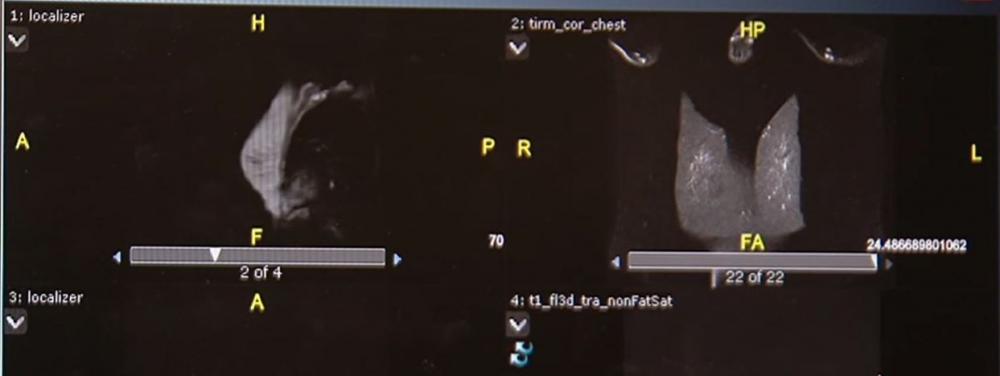

أظهرت نتائج أبحاث أميركية حديثة، سلامة لقاح جديد، قائم على الحمض النووي البلازميدي، للوقاية من سرطان الثدي.

فوفق الباحثين في معهد لقاح السرطان الأميركي التابع لجامعة واشنطن الطبية، أثبتت الدراسة غير العشوائية التي اعتمدت على تجارب سريرية لستٍ وستين مريضة تتراوح أعمارهن بين الرابعة والثلاثين والسابعة والسبعين، ممّن أصبن بسرطان الثدي الإيجابي المسمى علميا بـHER2، أن جرعات لقاح الحمض النووي التي خضعن لها كل ثلاثة أشهر، وفرت مناعة قوية تجاه الورم الرئيسي ومنعته من الانتشار.

الدراسة التي راقبت بيانات المريضات خلال أعوام وجدت أن المريضات اللواتي تم إعطاؤهنّ جرعاتٍ عالية من هذا اللقاح، تحسنت أيضا مناعتهنّ بشكل قوي مع انكماش قدرة البروتين المسبب لسرطان الثدي الإيجابي.